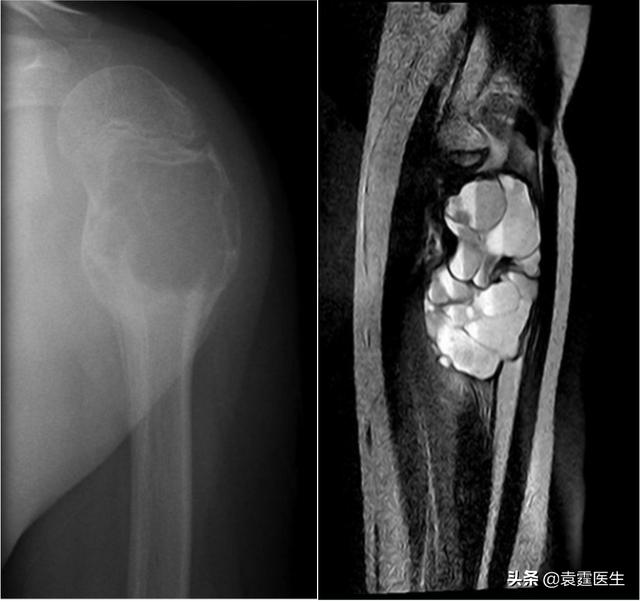

【骨头里的泡沫——动脉瘤样骨囊肿】我们先来看下面两张片子 。

平片、核磁共振

不难看出 , 在骨头里有一格一格类似泡沫一样膨大且透亮的结构 , 图2更是看上去像水泡一样长在骨头里 。 出现这种情况的原因呢 , 是因为长了骨肿瘤 , 这种肿瘤我们称之为动脉瘤样骨囊肿 。

动脉瘤样骨囊肿 , aneurysmal bonecyst, 有个非常好记的英文简写 , 叫ABC 。 动脉瘤样骨囊肿是一种好发于儿童和青少年的良性单发骨肿瘤 , 它的特点是在肿瘤内能看到如上图的均匀泡沫状透亮区 。 动脉瘤样骨囊肿是由大小不等充满血液腔隙组成的膨胀性溶骨性病变 , 囊壁为含骨样组织、骨小梁和破骨细胞型巨细胞的结缔组织 。 患者的症状是局部疼痛肿胀 , 功能障碍 , 如果病灶位于脊椎时 , 可以产生脊髓压迫症状 。